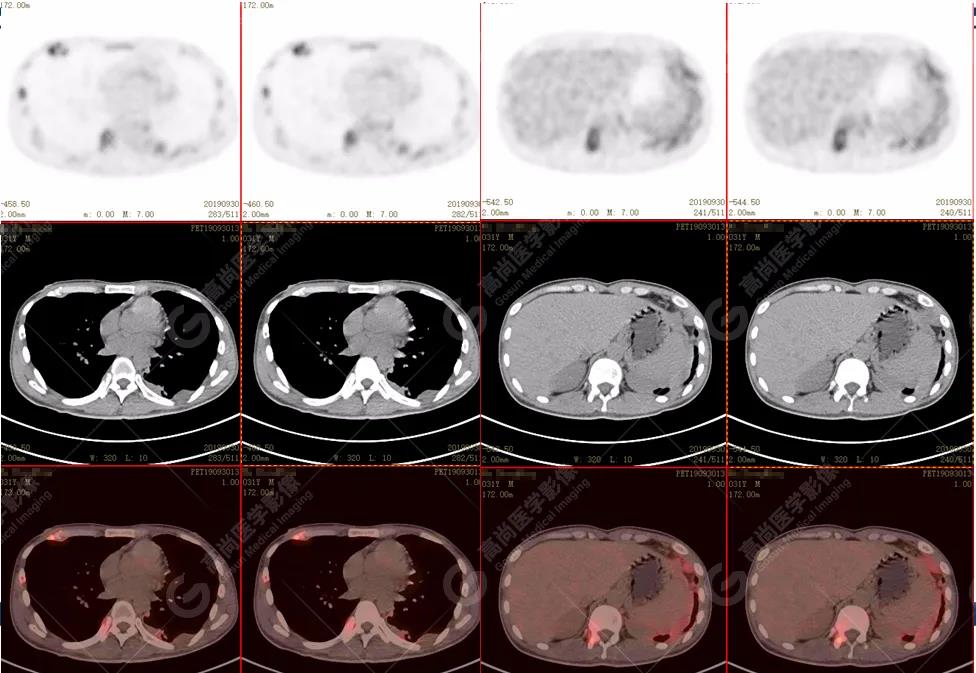

脊柱多發(fā)椎體及附件骨質破壞,代謝不均性增高

全身多處骨質破壞,代謝不均性增高

全身多發(fā)高代謝腫大淋巴結,中央代謝缺損

雙肺、左側胸膜多發(fā)結節(jié)影,全身多處骨質破壞,全身多發(fā)淋巴結腫大,代謝攝取不均勻性增高。

2.全身多系統(tǒng)、多形態(tài)、多發(fā)病灶(肺部、胸膜、淋巴結、骨),18F-FDG攝取不均性增高;

特征:肺部病灶簇狀分布,上葉尖段及下葉背段為著;腫大淋巴結分布不對稱,無融合、中央有壞死改變,與淋巴瘤、轉移瘤等有一定的鑒別診斷意義;

診斷意見:綜合考慮感染性病變(結核),建議相關實驗室檢查。